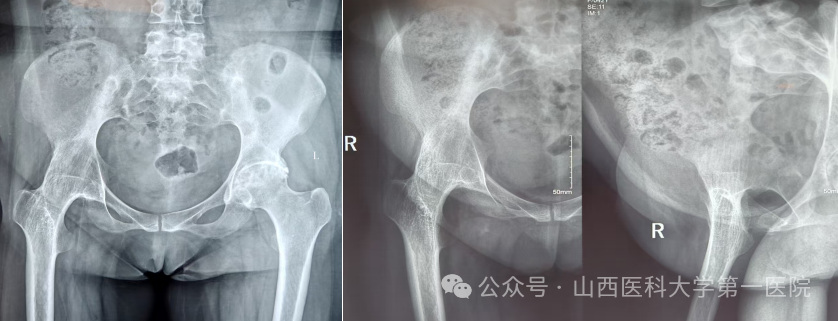

一名42岁的强直性脊柱炎患者,多年来饱受病痛折磨。随着病情进展,双侧髋关节逐渐“锈死”,无法弯腰、下蹲,甚至连坐下都成了奢望——吃饭只能站着,休息只能躺着,生活自理能力几乎丧失。接诊后,骨科杨自权主任团队对患者进行全面检查,发现患者不仅脊柱强直呈“板状腰”,双侧髋关节出现严重融合,而且双膝、双踝关节功能明显下降,手术难度极大。

图片